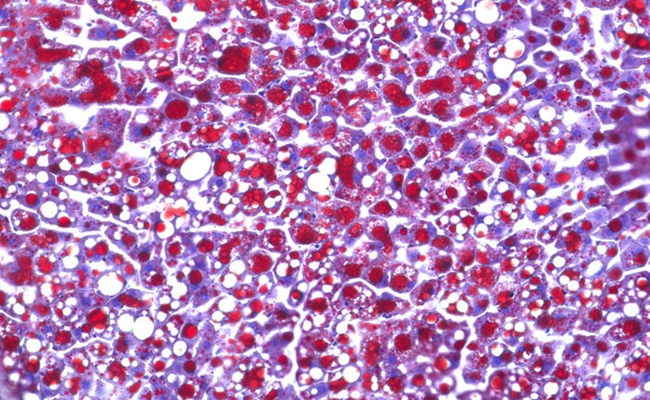

هذا في حين أصيبت فئران مجموعة المقارنة، التي عولجت بنفس الطريقة وبنفس العقار، بسكري الستيرويد. بل أنها صارت تعاني من البدانة ومن زيادة الدهون في الدم، كما اصيبت أكبادها بالتشحم.